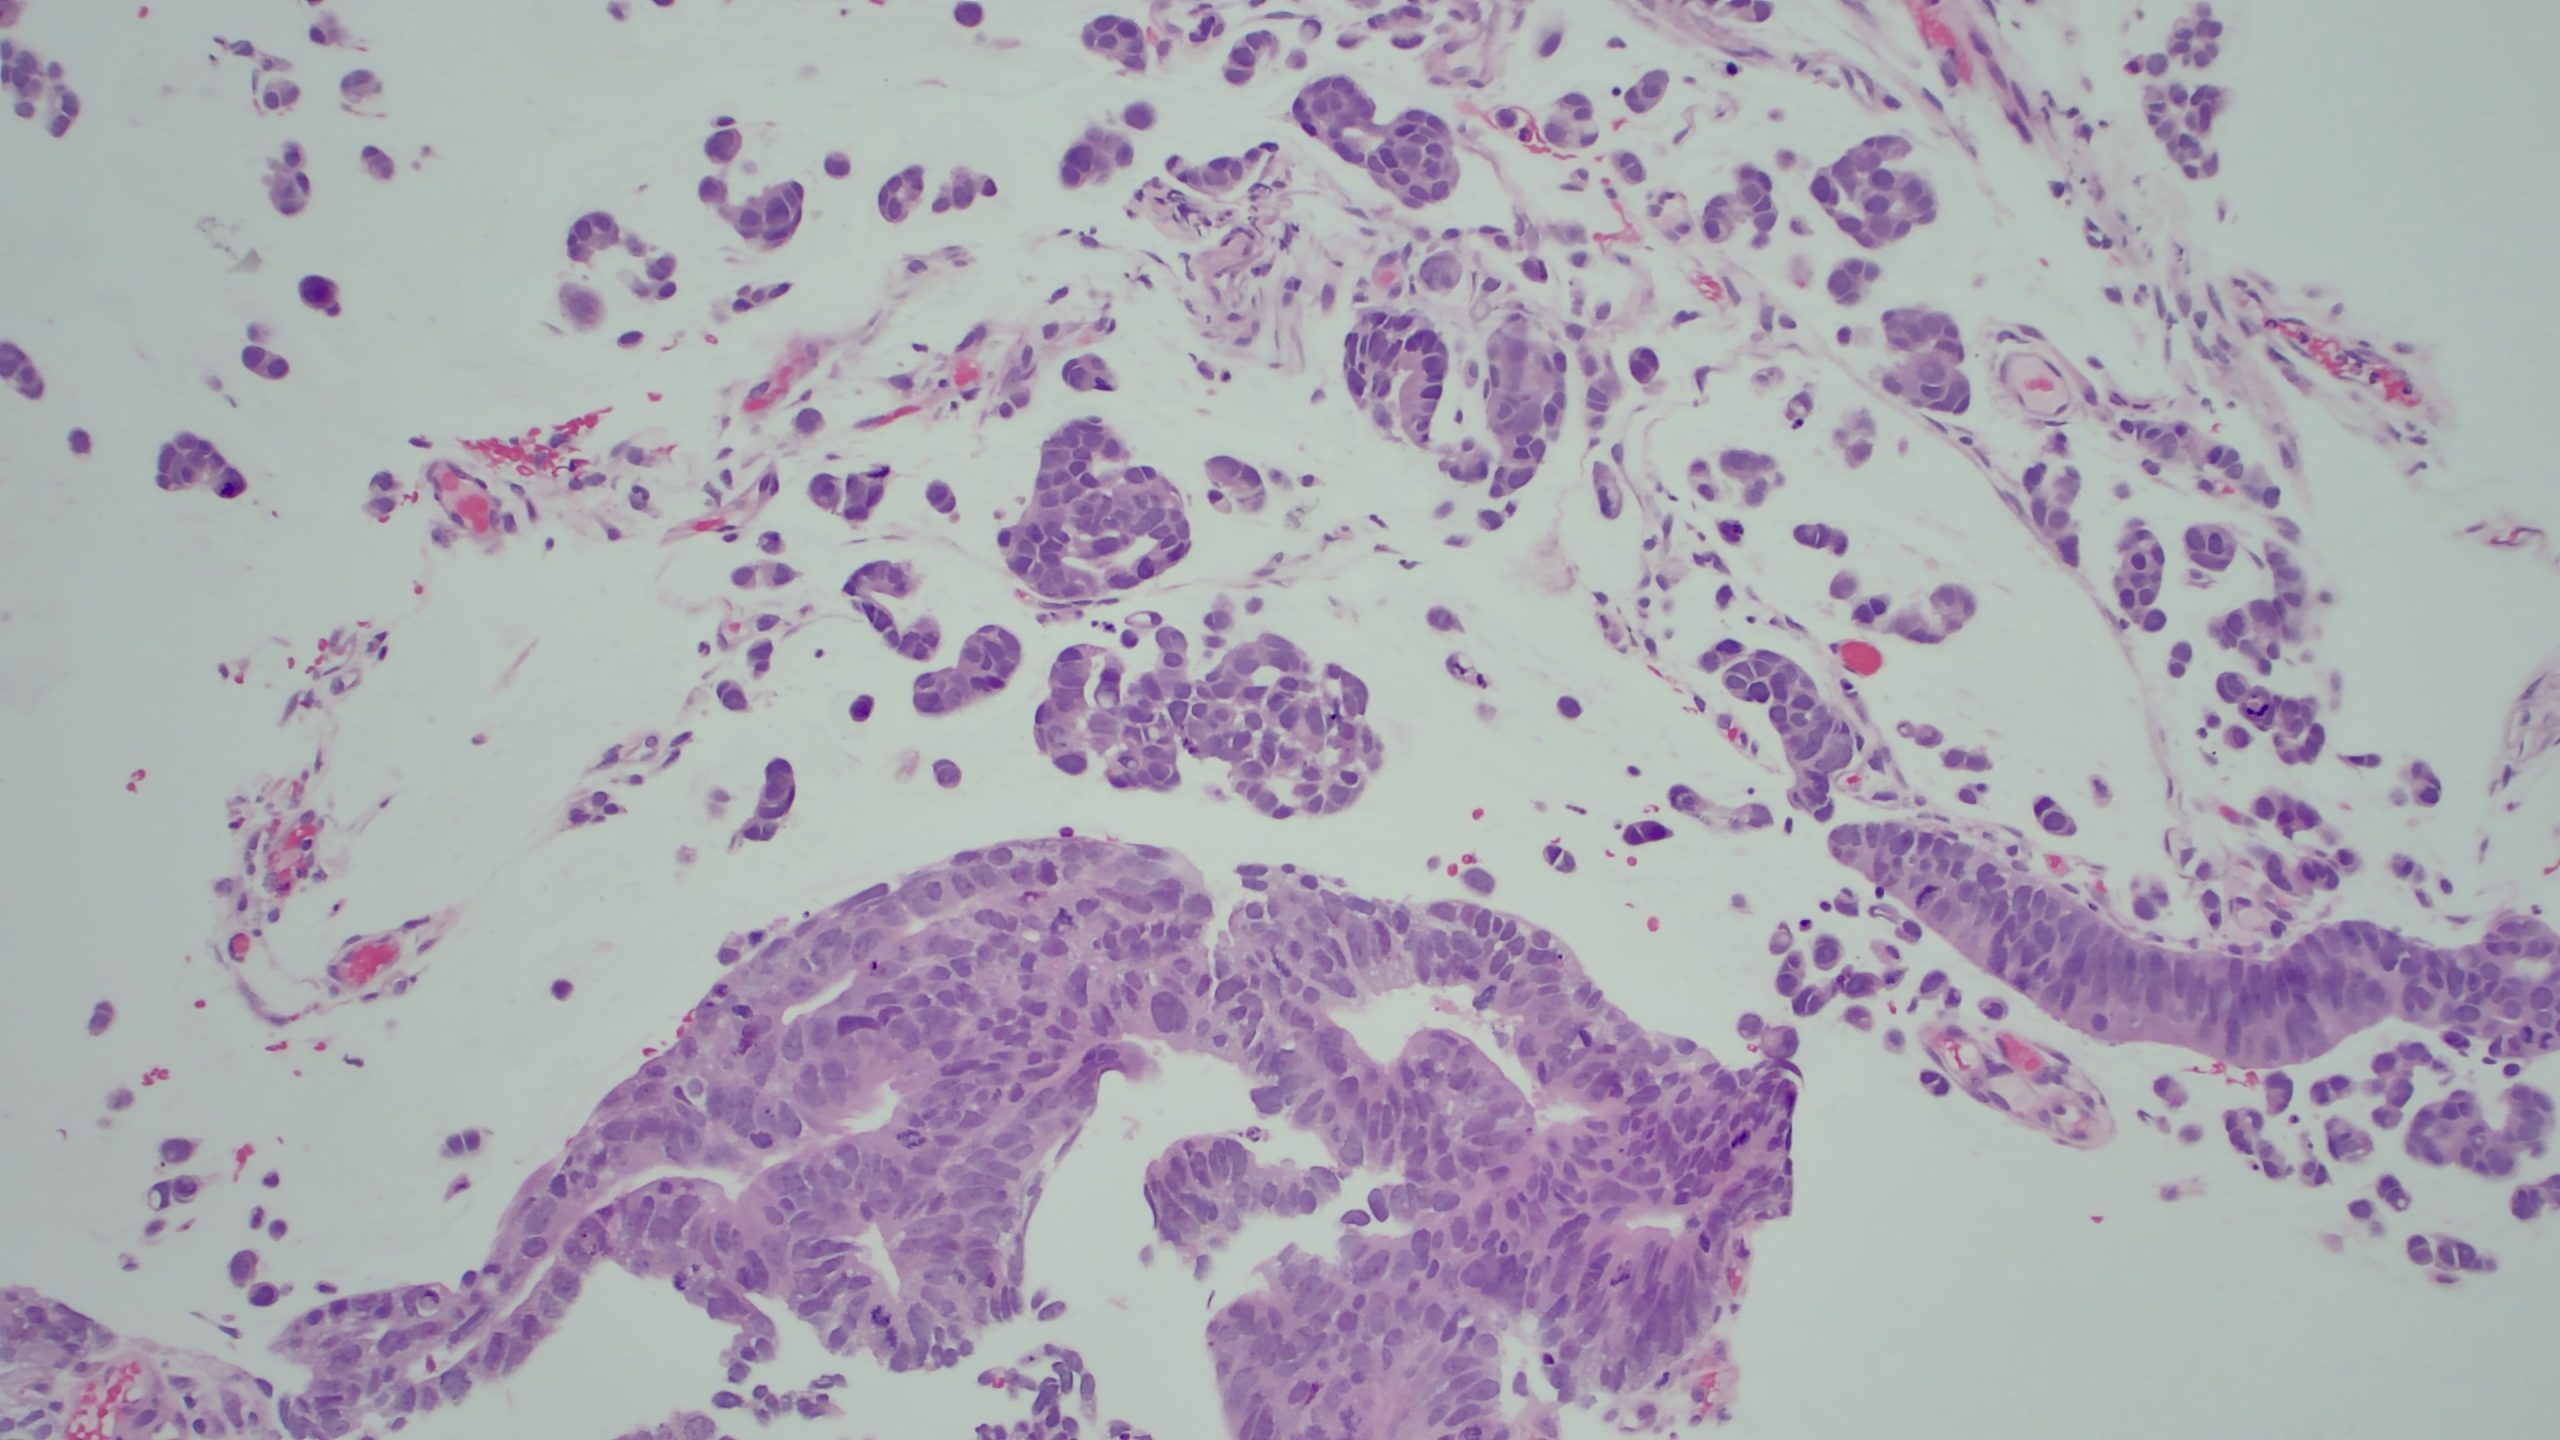

Case Presentation: A 49-year-old female with no known past medical history presents with worsening symptoms of abdominal discomfort, bloating, and shortness of breath for one month. Upon presentation, vitals were significant for tachycardia. A CT scan of the abdomen and pelvis showed hepatic steatosis with a large volume of ascites. A paracentesis was performed and six liters of fluid were removed and sent for microbiological and cytologic analysis. Patient received albumin and was discharged. Three days later, the pathology results returned and were consistent with adenocarcinoma with mucinous features. The patient was called back by the hospitalist to return for further workup. CDX2 and CK20 staining were suggestive of malignancy of colorectal origin. A pelvic ultrasound was ordered to rule out ovarian tumors and showed soft tissue nodules within the right adnexa, suggestive of metastatic peritoneal implants. A CT scan of the abdomen and pelvis with contrast showed soft tissue fullness involving the sigmoid colon and an underlying colonic neoplasm, as well as a moderate to large amount of ascites with probable omental caking. A colonoscopy was performed and revealed 30 cm mass in the sigmoid colon. Biopsy reports revealed poorly differentiated colorectal adenocarcinoma with signet ring cell morphologic features with negative microsatellite instability. Tumor markers were positive for PMS2, MLH1, MSH2, and MSH6. The patient was determined to be a candidate for the FOLFOX6 chemotherapy regimen.